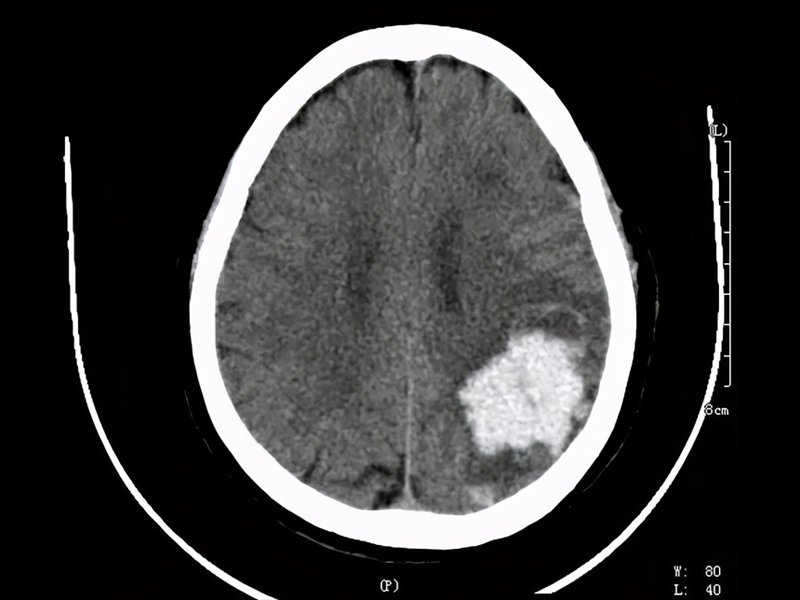

據報道,這名程序員吳先生從事技術工作,月薪高達 3 萬元人民幣,但每天的工作時間從早上 7 點持續到凌晨 1 至 2 點,長期處於極度疲勞狀態。今年年初,他因腦幹出血 5 毫升陷入昏迷,昏迷長達 15 天,在 ICU 搶救 28 天後才逐漸恢復意識。隨後,他又轉入康復醫院進行 70 多天的治療,目前已恢復約 70% 的身體功能,但仍無法完全康復。